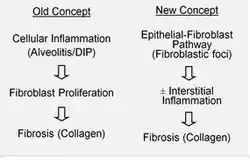

Acredita-se que a FPI seja o resultado de um processo aberrante de cicatrização de feridas, incluindo/envolvendo a deposição anormal e excessiva de colágeno (fibrose) no interstício pulmonar, com inflamação mínima associada.[17] Suspeita-se que a senescência celular seja uma causa central, uma crença que é apoiada pelos benefícios observados em pacientes que receberam terapia senolítica.[18][19][20]

A hipótese é que a lesão inicial ou repetitiva na FPI ocorra nas células pulmonares, chamadas células epiteliais alveolares (pneumócitos), que revestem a maior parte da superfície alveolar.[21] Quando os pneumócitos do tipo I são danificados ou perdidos, acredita-se que os pneumócitos do tipo II sofram proliferação para cobrir as membranas basais expostas. No reparo normal, os pneumócitos hiperplásicos do tipo II morrem e as células restantes se espalham e passam por um processo de diferenciação para se tornarem pneumócitos do tipo I. Em condições patológicas e na presença do fator de transformação do crescimento beta (TGF-β), os fibroblastos se acumulam nessas áreas de dano e se diferenciam em miofibroblastos que secretam colágeno e outras proteínas.[21] Na classificação atual da patogênese da FPI, acredita-se que ela ocorra por meio da formação de uma lesão de PIU (pneumonia intersticial usual), que então passa pela condição patológica característica da FPI mencionada anteriormente.[22] Outros mecanismos de lesões repetidas propostos indicam que a FPI pode resultar não apenas de uma lesão pneumonia intersticial idiopática (PII), mas também de lesões pneumonia intersticial não específica (PINE) e lesão alveolar difusa (LAD),[23] ou de uma combinação de várias delas.

No passado, acreditava-se que a inflamação era o primeiro evento no início da formação de cicatrizes no tecido pulmonar. Descobertas posteriores mostraram que o desenvolvimento de focos fibroblásticos precede o acúmulo de células inflamatórias e a consequente deposição de colágeno.[24] Esse modelo patogenético é indiretamente apoiado pelas características clínicas da FPI, incluindo um início insidioso ao longo de vários anos, exacerbações agudas relativamente infrequentes e falha na resposta à terapia imunossupressora.[17][25] No entanto, alguns pesquisadores acreditam que a doença é multimecanística, em que o desencadeamento da doença pode resultar de anormalidades em qualquer número de vias de cicatrização de feridas, incluindo a resposta inflamatória.[23] Tais anormalidades poderiam ocorrer em qualquer número das nove vias implicadas (cascata de coagulação, vias antioxidantes, apoptose, citocinas inflamatórias, angiogênese e remodelação vascular, fatores de crescimento, surfactante e fatores reguladores da matriz),[23] e que, por meio de uma investigação mais aprofundada de todas as nove, novas terapias e abordagens poderiam ser propostas em uma base única ou caso a caso, caso as tentativas de tratar ou contornar complicações em qualquer via não fossem bem-sucedidas. Várias terapias que têm como alvo a ativação de fibroblastos ou a síntese da matriz extracelular estão atualmente em testes iniciais ou estão sendo consideradas para desenvolvimento.